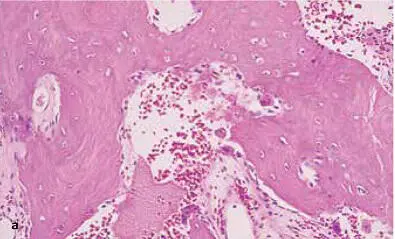

FIG 1-16 (a and b) At about 6 weeks, the graft begins a major resorption-remodeling cycle in which osteoclasts resorb the disorganized immature bone and release BMP and insulinlike growth factors, thus inducing formation of new bone that will mature during function. (Reprinted with permission from Marx and Garg. 1)